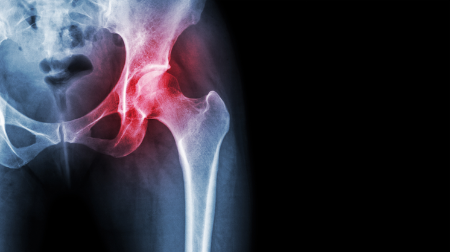

Esta enfermedad conocida también como necrosis avascular, consiste en la falta de vascularización y aporte sanguíneo al hueso en la cabeza del fémur.

Imagen en alta resolución. Este enlace se abrirá mediante lightbox, puede haber un cambio de contexto"Puede curar espontáneamente o llevar a una deformidad del hueso y de la articulación, llegando a producir dolor intenso e incapacidad para caminar. Así en muchas ocasiones requiere implantar una prótesis total de cadera. La ONCF es una enfermedad de causa desconocida en la mayoría de los casos, pero está muy relacionada con algunos factores como la ingesta de alcohol o tratamientos con corticoides", afirma el doctor Gray.

La bibliografía científica muestra que ya en la epidemia de SARS de 2003 (neumonía atípica grave causada por un virus de la familia de los coronavirus), los pacientes infectados que sufrieron patología respiratoria grave, tratados con corticoides que a su vez tenían dolor articular, presentaban necrosis avascular un 39% de los varones y un 19% de las mujeres. "Esto se había diagnosticado a los 3 meses desde el comienzo de la enfermedad respiratoria y de su tratamiento. La necrosis ósea en este momento se encontraba en sus primeras fases", asevera el experto.

A la vista de los resultados observados en 2003, según el doctor Gray Laymon, podemos deducir que actualmente nos encontramos ante un probable aumento de la incidencia de necrosis ósea en los pacientes que han sufrido problemas respiratorios graves por Covid-19 que todavía no se ha mostrado, pero que, si se repite lo ocurrido entonces, aparecerá en los próximos meses.

Tal y como explica el doctor, la necrosis avascular tiene un curso impredecible desde la curación total hasta la potencial destrucción de la articulación, con la necesidad de implantar una prótesis de cadera en ese caso. "Sin embargo, en las primeras fases, existen tratamientos médicos, físicos y quirúrgicos que, aunque no siempre, pueden cambiar su curso hacia la curación".